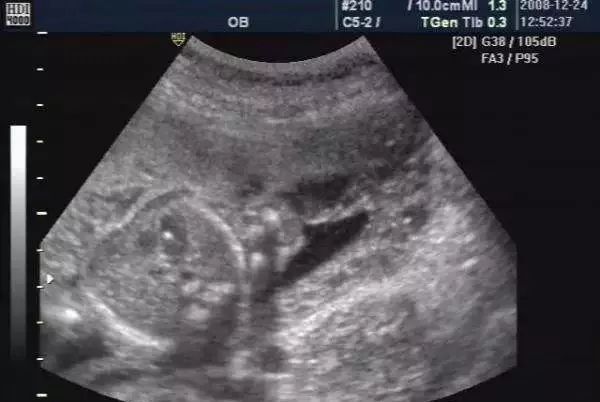

随着医学的进步,B超机的分辨率越来越高。以前孕检中看不到的胎儿情况看的越来越清楚了,有时候没有什么大问题,可人家B超医生看见什么就要报告什么,结果让很多准妈妈非常担心。比如在怀孕期间宝宝做了B超检查,发现胎儿左心室里面有一个强光斑,这可是个不少孕妈都会遇到的揪心问题。

其实胎儿心室内点状强回斑是一个声像图表现,而不是一种心脏畸形,更不是一种心脏异常诊断。

胎儿左心室的强光斑又称强光点或者强回声,其实不仅仅是左心室,右心室也可以发现,胎儿心室内这种强回声光斑,一般是:胎儿心室内腱索增厚形成的强回声反射、乳头中央矿物沉积、乳头肌腱索不完全穿孔等。